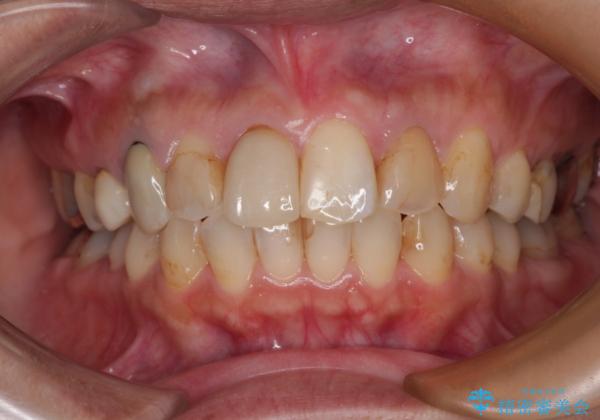

術中や仕上がりに特に大きなトラブルはなく、スムーズに治療を終えることができました。

【モニター】処置歯の多い歯列 インビザラインでデコボコを整える